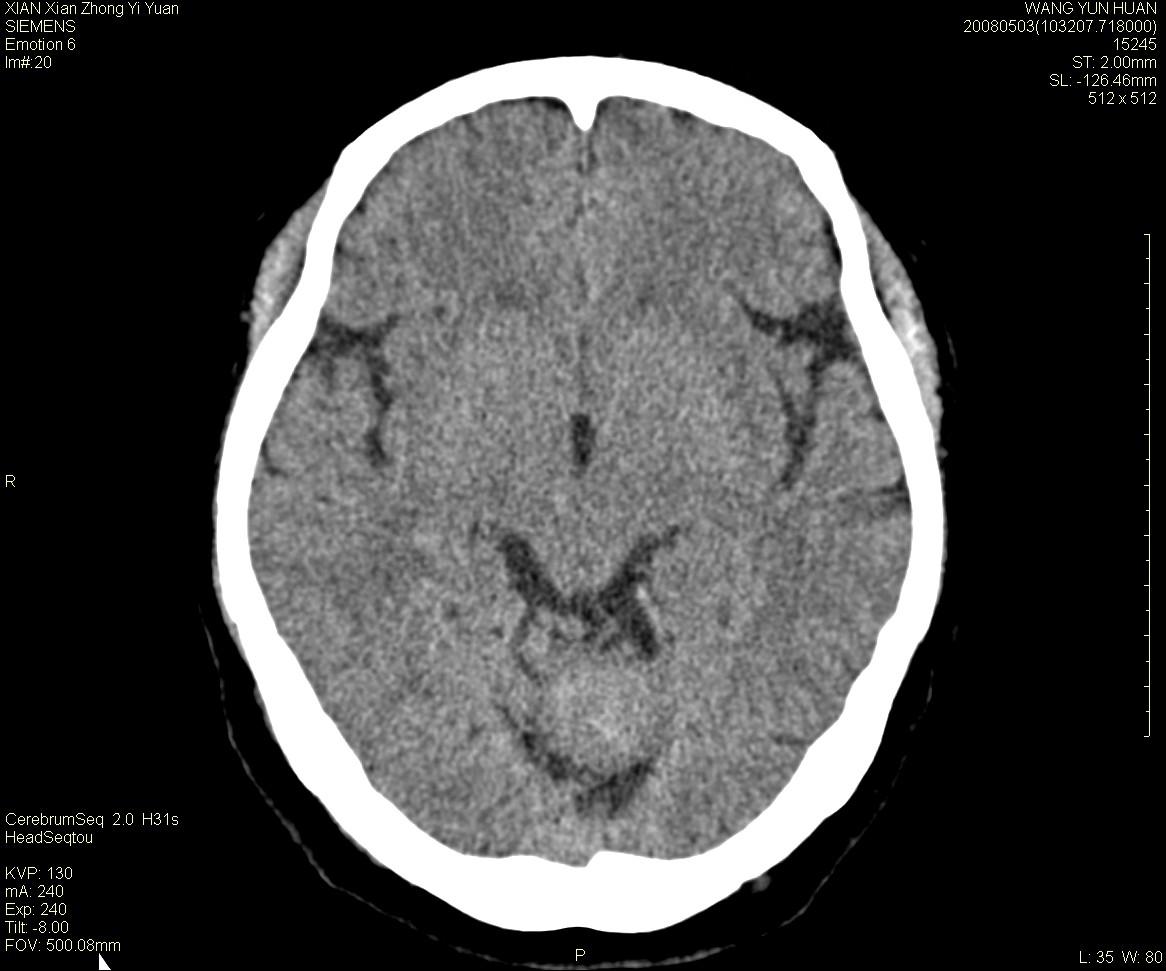

标题: CT13219:(补充强化)请会诊,患者女,60岁,头晕,大家看 [打印本页]

标题: CT13219:(补充强化)请会诊,患者女,60岁,头晕,大家看

病灶显示轻度强化,ct增加4hu左右,大家看是什么肿瘤.

强化后动脉期及延迟2分钟,五分钟图像

小脑蚓部囊型肿块,内有实性结节及钙化点。增强后囊壁及结节轻度强化。

考虑蚓部星形细胞瘤(ⅱ级可能性大)。

小脑蚓部肿块,周围无明显占位效应及水肿带,增强轻度强化,考虑低分级星形细胞瘤。